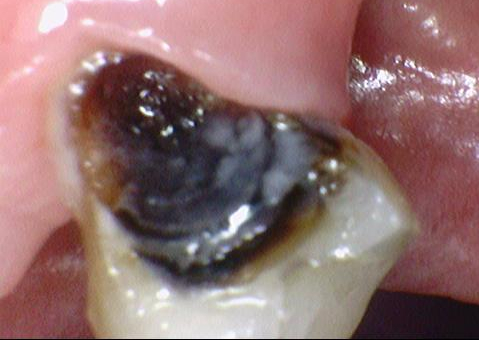

2번의 경우는 위의 카메라로 찍은 사진처럼 치아가 엄청 많이 썩어있었지만

치아 주변의 뼈는 비교적 많이 녹지 않았고 치아도 흔들리는 상태는 아니었기 때문에

1번의 경우는 발치 후 뼈가 어느정도 찰때까지 기다렸다가 임플란트를 하는 것이

2번의 경우는 만약 임플란트를 한다면 발치하면서 임플란트를 하는 것이

가능할 수 있다 하겠습니다.